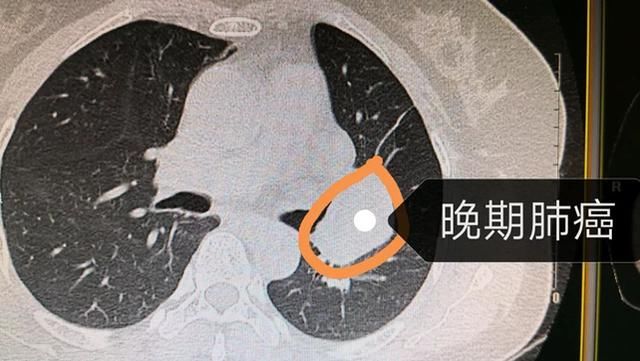

肺内结节当中最危险的一种是专业上称为毛玻璃样或磨玻璃样的结节,影像学专业描述为肺部毛玻璃样结节或肺部磨玻璃样结节,且模糊不清,此类结节较危险。通过大量数据统计

哪种肺部结节最危险 您的浏览器不支持播放视频,请升级。 视频内容 肺结节最危险,即发生恶变的概率更高,具体如下: 1、肺结节越大,恶性的可能性越大,结节直径在1cm以上,恶